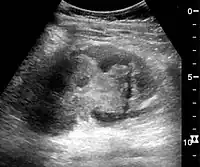

These may include urine sediment analysis, renal ultrasound and/or kidney biopsy. Indications for kidney biopsy in the setting of AKI include the following:[15]

In medical imaging, the acute changes in the kidney are often examined with renal ultrasonography as the first-line modality, where CT scan and magnetic resonance imaging (MRI) are used for the follow-up examinations and when US fails to demonstrate abnormalities. In evaluation of the acute changes in the kidney, the echogenicity of the renal structures, the delineation of the kidney, the renal vascularity, kidney size and focal abnormalities are observed.[16] CT is preferred in renal traumas, but US is used for follow-up, especially in the patients suspected for the formation of urinomas. A CT scan of the abdomen will also demonstrate bladder distension or hydronephrosis. However, in AKI, the use of IV contrast is contraindicated as the contrast agent used is nephrotoxic.